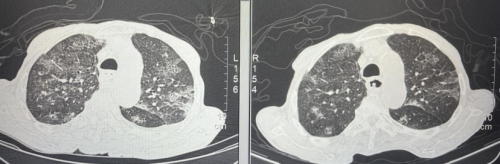

入院时CT: